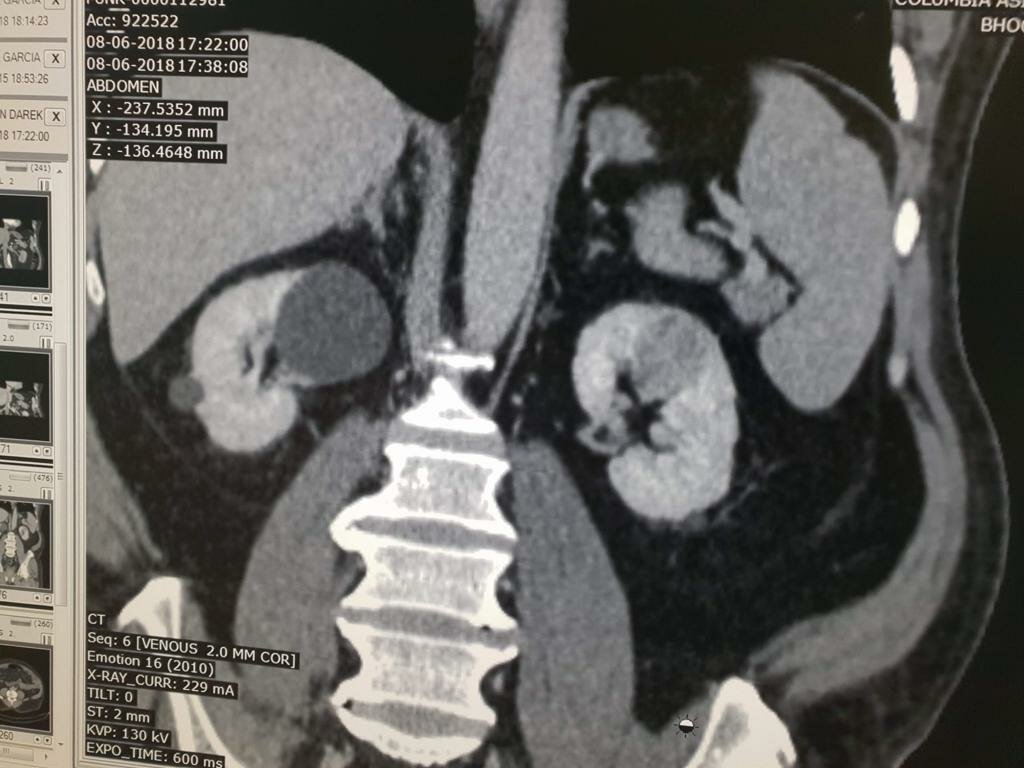

56 Yr old Male patient came with pain in the abdomen best urologist in Pune, was Dr. Bhoopat Bhati. diagnosed him and the concluded that the patient h...